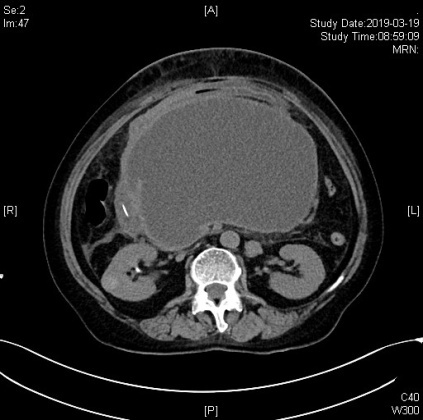

腹部高高隆起如怀胎十月、憋喘胸闷状况严重且完全不能进食,这让68岁的董阿姨痛苦不堪。近日,她因反复胰腺炎发作并发了胰腺假性囊肿,在当地医院治疗效果不理想,而假性囊肿又在持续增大,于是转诊至我院东院区。此时,CT提示囊肿大小已达12X18cm,临近的器官已经受到了推挤。

术前CT